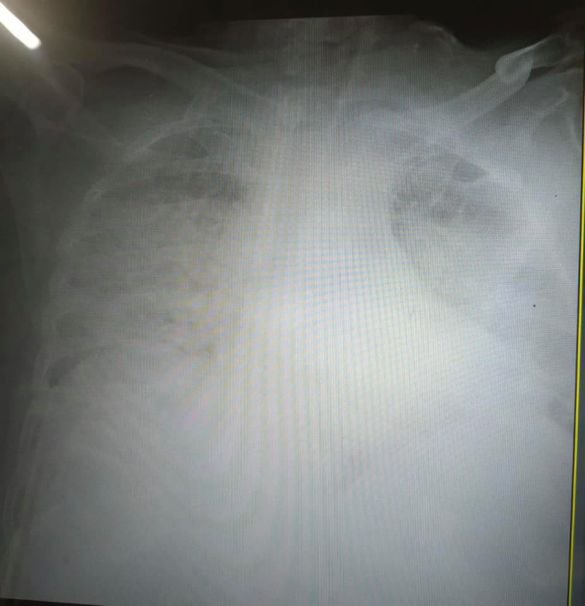

Медики Львова показали, який вигляд мають легені, уражені Covid-19.

Фото уражених коронавірусом легенів Ірина Заславець виклала у Facebook. Орган на знімку перетворився на суцільну світлу пляму.

"Це одні з найстрашніших легенів, які я бачила в житті", - сказала очільниця реанімації клінічної лікарні швидкої медичної допомоги Львова", — написала Заславець у дописі.

Легені померлих внаслідок Covid-19 відрізняються від типового стану і більше нагадують печінку. Усередині легені змінюються через тромби. "Коронавірусну" пневмонію ні з чим не переплутаєш, розповіли паталогоанатоми Львівського обласного моргу.